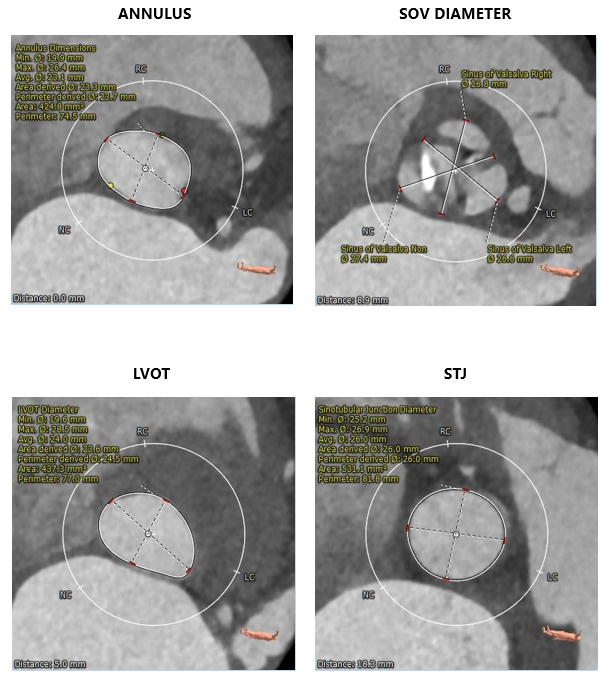

术前CT评估

主动脉根部测量

CT特点:三叶式主动脉瓣,瓣叶轻度钙化,钙化主要位于无窦瓣叶边缘及左右窦交界处,瓣叶显著增厚伴左右窦部分融合;瓦氏窦、窦管交界内径偏小,升主动脉内径可;右冠开口高度可,左冠偏低,瓣叶冗长;非横位心。

瓣上测量

瓣上测量:瓣叶钙化较轻、增厚显著,瓣膜锚定难度稍高;左右窦交界纤维性融合存在一定限制。